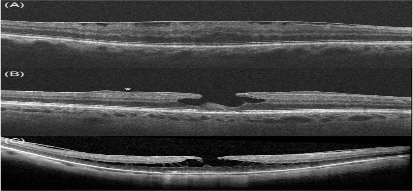

Hình ảnh trên OCT của màng trước võng mạc và các khái niệm có liên quan: A- màng trước võng mạc, B- lỗ lớp hoàng điểm cùng với tăng sinh trước võng mạc (dấu sao), C- tách lớp võng mạc

Sự thay đổi từ phương pháp soi sinh học bằng đèn khe truyền thống sang phương pháp chụp ảnh cắt lớp võng mạc thế hệ SD-OCT đã dẫn đến việc định nghĩa lại các bệnh võng mạc vốn khó phân biệt với nhau. Giờ đây các bác sĩ có thể phân định chính xác các tổn thương sau đây:

- Màng trước võng mạc

- Tăng sinh trước võng mạc

- Lỗ lớp hoàng điểm

- Tách lớp võng mạc vùng hoàng điểm

Sự nhất trí về các định nghĩa cho các tình trạng võng mạc này đã làm giảm bất đồng trong chẩn đoán của các bác sĩ và thúc đẩy áp dụng thêm nhiều công nghệ mới để điều trị ERM.